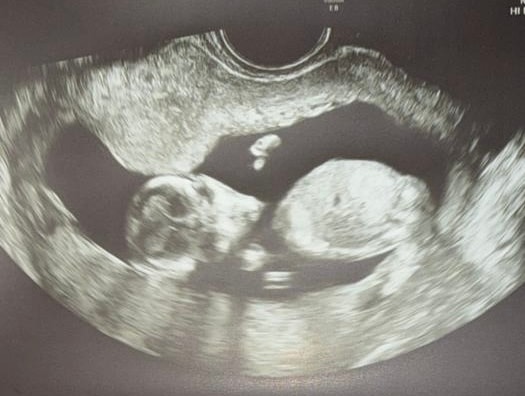

По УЗИ 20.1

Мальчик, снова сыночек. Изначально знала, что будет он.

Вес 333 грамма.